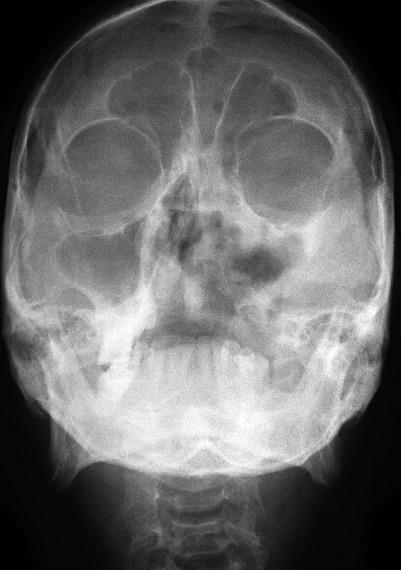

Mucormycosis is a rare, highly lethal opportunistic fungal disease affecting immune compromised and diabetic patients. Mucormycosis is considered as the 3(rd) most common invasive mycosis after candidiasis and aspergillosis in debilitating patients. It is caused by the filamentous fungi of the class zygomycetes. The infection usually begins in the nose due to inhalation of fungal spores. This fatal fungal disease needs a prompt and early definitive diagnosis, aggressive surgical therapy and high dose anti-fungal therapy. Here, we present a case report of Mucormycosis in a 64 year elderly diabetic male patient who was previously operated for myiasis and also the extensive review of the literature of the mucormycosis.